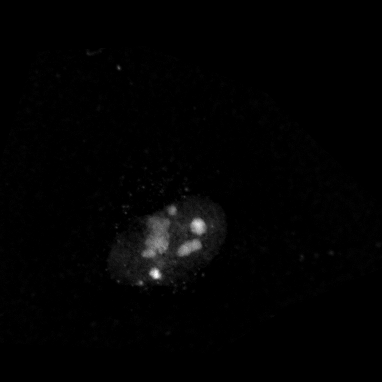

Microscopy techniques are employed to capture subcellular localization images of proteins in a cell, which were previously analyzed using traditional wet methods. However, advances in microscopy techniques have brought an avalanche of medical images in a considerable amount; hence, manual analysis and processing of these medical images become nearly impossible for biologists. Moreover, a subjective inspection of images may lead to errors in decision-making process shao2017deep ; tahir2011protein ; kreft2004automated . It is highly likely that the images generated for proteins of the same class may look visually different (see Figure 1). Similarly, proteins belonging to two different classes may look alike. Such a situation leads to the poor performance of classification systems. These problems are resolved by applying different hand-crafted feature extraction strategies to capture multiple views from the same image tahir2016protein . Hence, this is a cumbersome job and may fail to discriminate with high accuracy.

Prediction confidence: We compare the prediction confidence of traditional classifiers trained on Yeast and HeLa datasets against our PLCNN on four images as shown in Figure 11. Each image has the prediction probabilities for each algorithm underneath. The red color shows when the prediction is incorrect, whereas the green is for the correct outcome. It can be observed that our method predicts the correct labels with high confidence, while the probability is very low when the prediction is incorrect. The image in the first column in Figure 11 is very challenging due to minimum texture and almost no structure. All the methods failed to identify the type of protein in the mentioned image correctly. However, the competing methods prediction scores are much higher than ours. Similarly, our algorithm confidence is always high when the prediction is correct and low when it is incorrect. This shows the learning capability of our network.

![]() |

|

| AlexNet | 0.32 | 0.57 | 0.79 | 0.82 |

|---|---|---|---|---|

| ResNet | 0.69 | 0.68 | 0.49 | 1 |

| DenseNet | 0.60 | 0.79 | 0.75 | 0.90 |

| PLCNN | 0.26 | 0.88 | 1 | 1 |